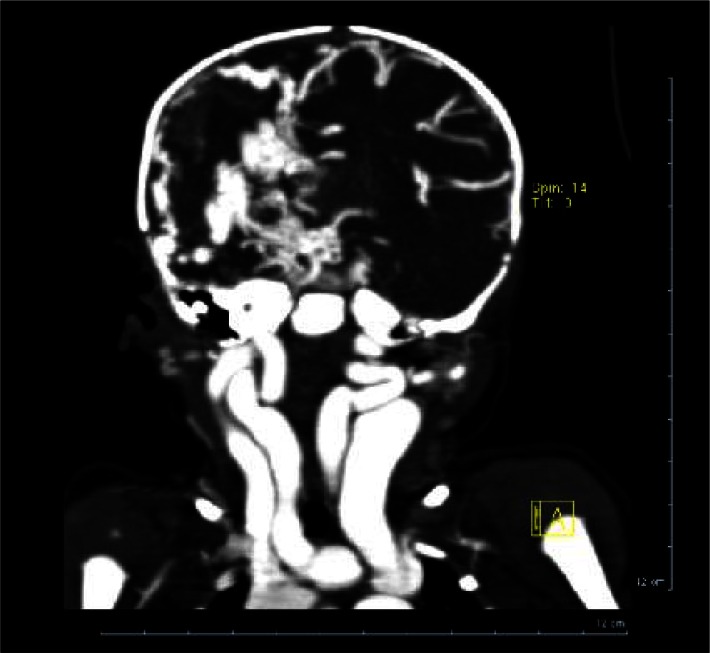

Fig. 3.

Multislice CT scan with contrast. Coronal view showing dilated neck arteries and veins and atrophy of right hemisphere